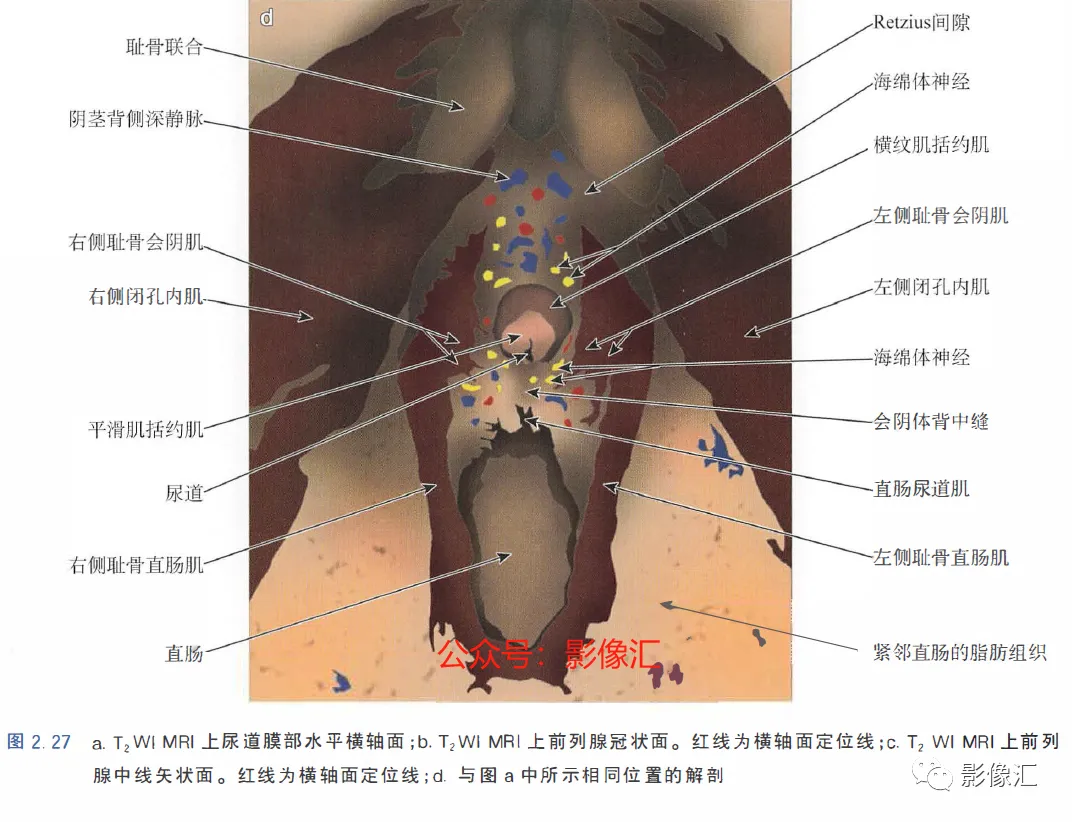

前列腺尖部是用于表示前列腺腺体尾侧(最下方)的术语,与尿道膜部密切接触。前列腺尖部可显示出不同的形态:圆环形或腹侧,背侧或两侧突出(图2. 9和图2.10) ,了解前列腺尖部形态的重要性主要在于两点:(1)前列腺尖部或多或少与EUS(尿道膜部的横纹肌纤维)头侧区域重叠(或覆盖),这些纤维部分融入前列腺尖部(图2.11)。在接受根治性前列腺切除术的患者中,有必要采用能够外翻(exteriorising)和解剖这部分横纹肌纤维的手术技术, 以保持控尿功能(图2.12)。(2)在根治性前列腺切除术中必须避免阳性边缘 。值得注意的是,在尖部水平,腺体组织仅为外周带组织,尖部仅前缘一小部分为AFMS。此外,前列腺尖部构成所谓的梯形区域的顶部,这是众所周知的解剖薄弱区域,在该区域前列腺癌可更易侵犯至前列腺间隙(图2.8)。在其前外侧,前列腺尖部由外括约肌群覆盖,与AFMS及从膀胱颈延伸来的由平滑肌构成的逼尿肌群相融合(图2. 13)。前列腺尖部尾侧与尿道膜部起始部相延续。男性的尿道膜部被认为是位于前列腺尖部和尿道球部之间的尿道部分,长度约为1cm。其内有尿道内括约肌(IUS)和尿道外括约肌(EUS)。IUS从膀胱颈(此处最厚)延伸到尿道球部,沿尾侧方向厚度逐渐减小。IUS环尿道膜部,由双层平滑肌纤维组成,包括内层纵行肌和外部的环形肌(图2. 13和图2. 14)。IUS的神经支配来自自主神经、交感神经和副交感神经系统。下腹下神经丛负责前列腺、前列腺尖部和尿道膜部的所有自主神经支配。其终末支沿内侧走行达耻骨上肌,外侧走行达尿道膜部的EUS,在腹侧构成所谓的阴茎海绵体神经(负责勃起机制)和尿道海绵体神经(负责尿道膜部黏膜的自主神经传入,直接与控尿机制有关(图2 . 13 和图2. 14)。EUS构成横纹肌平面(横纹肌纤维),在尿道膜部水平围绕IUS,在前列腺尖部的前外侧上扩展,并在该水平上构成所谓的EUS围裙(图2. 13)。其肌纤维主要是I 型(即没有肌梭),尽管强度低,但专门负责长时间收缩。EUS的功能在于排尿间期保持尿道腔塌陷,从而防止无意识的尿液渗漏。EUS最厚处位于尿道膜部水平,厚度向头侧逐渐减小,最终构成前列腺围裙。该围裙以Ω(希腊字母“欧米伽”)形围绕尿道膜部,而后正中不包绕, 形成“后正中脊”(图2. 13 和图2. 14)。此外,EUS的部分横纹肌纤维融入到前列腺尖部的下部,位于精阜下方,融入纤维的多少依赖于前列腺尖部形态(图2. 11) 。EUS的神经支配和动脉供血分别来自外阴神经和外阴内动脉。该神经为躯体神经,因此EUS可随意控制。外阴内神经和动脉均向头侧走行,至会阴深横肌处,发出分支支配EUS最尾侧部分,随后形成阴茎背侧神经脊背侧动脉。前列腺尖部与支配EUS的外阴内动脉的分支之间距离为3~13mm (图2. 13)。IUS和EUS构成所谓的控尿被动及内在因素。它们的功能基本上是“塌陷”尿道至“后正中脊”,这样可防止排尿间期无意识的尿液“泄露”(图2.11和2.13)。阴茎海绵体神经在前列腺周围筋膜的后外侧及前外侧走行。手术操作时保留这些外侧神经对于确保前列腺根治术后勃起功能的恢复是至关重要的。会阴体是一纤维肌性结构,难以在解剖上进行评估,其功能是支持所有构成会阴部及支撑盆腔脏器的肌肉及腱膜结构。对于控尿,会阴体形成一固定的底盘,通过将EUS的横纹肌平面压至底盘处,从而可使EUS正确发挥功能,这样在排尿间期可以正确地使尿道塌陷。会阴体由以下结构组成(图2.13)和图2.14)。